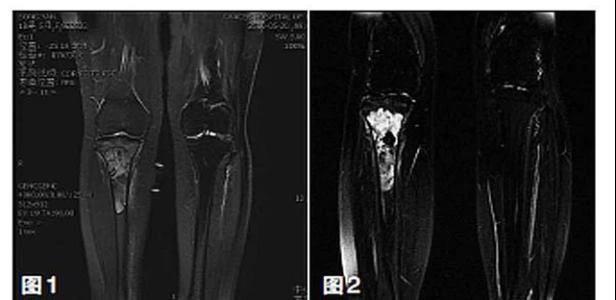

保肢治療指經(jīng)典型骨肉瘤在多學(xué)科團(tuán)隊(duì)醫(yī)生共同努力下完成的新輔助化療、保肢手術(shù)和輔助化療等一系列治療總稱,其目的是在提高患者生存率的前提下,減少局部復(fù)發(fā)、盡量保留良好的肢體功能。肢體經(jīng)典型骨肉瘤保肢治療方法如下圖所示:

新輔助化療的目的是盡早殺滅遠(yuǎn)處微小轉(zhuǎn)移灶,縮小腫瘤及周圍炎性水腫反應(yīng)區(qū),以利于后續(xù)的保肢手術(shù);觀察腫瘤對化療的敏感性,為進(jìn)一步指定個(gè)體化的術(shù)后化療方案奠定基礎(chǔ)。骨肉瘤新輔助化療下的保肢治療如下圖所示: